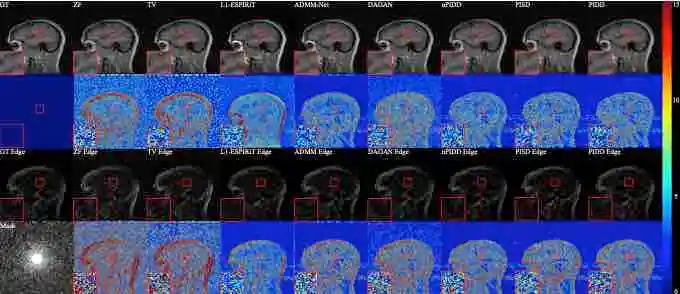

| Edge-Enhanced Dual Discriminator Generative Adversarial Network for Fast MRI with

Parallel Imaging Using Multi-view Information Jiahao Huang, Weiping Ding, Jun Lv, Jingwen Yang, Hao Dong, Javier Del Ser, Jun Xia, Tiaojuan Ren, Stephen Wong, Guang Yang Applied Intelligence 2021 [Paper] |